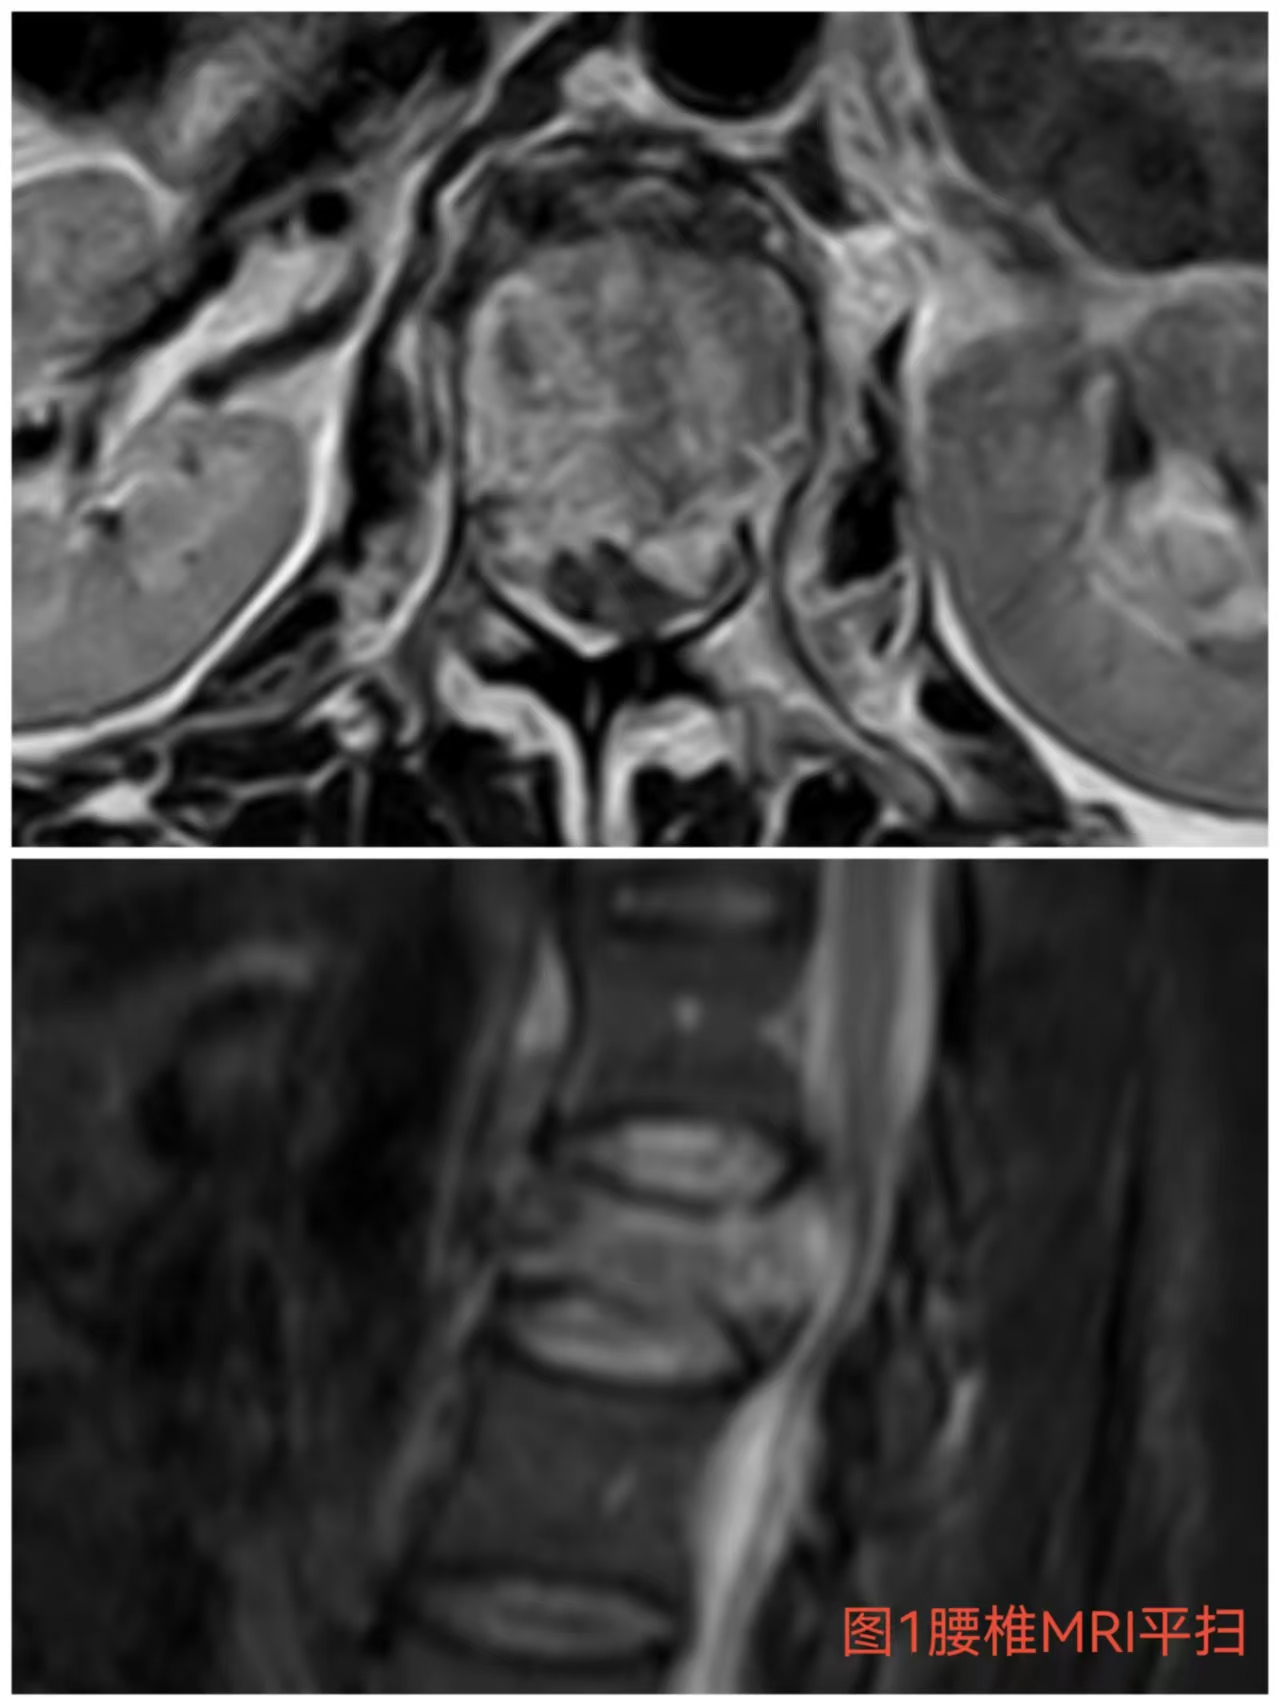

入院時(shí)患者躺在床上不能動(dòng)彈,眼神中透漏著深深的無(wú)助,對(duì)于她來(lái)說(shuō)這種傷情無(wú)疑是沉重的,尤其是腹股溝以下感覺(jué)消失、雙下肢肌力0級(jí),這意味著其下肢無(wú)法活動(dòng)及站立,仿佛被命運(yùn)按下了暫停鍵;與病人及家屬充分溝通病情后,第一時(shí)間給予對(duì)癥治療,監(jiān)測(cè)患者生命體征,行腰椎核磁檢查(圖1)提示:腰1椎體爆裂性骨折,椎體后緣塌陷致骨性椎管狹窄,壓迫脊髓神經(jīng),結(jié)合患者病情及輔助檢查可診斷為:“L1椎體爆裂性骨折伴雙下肢截癱”。